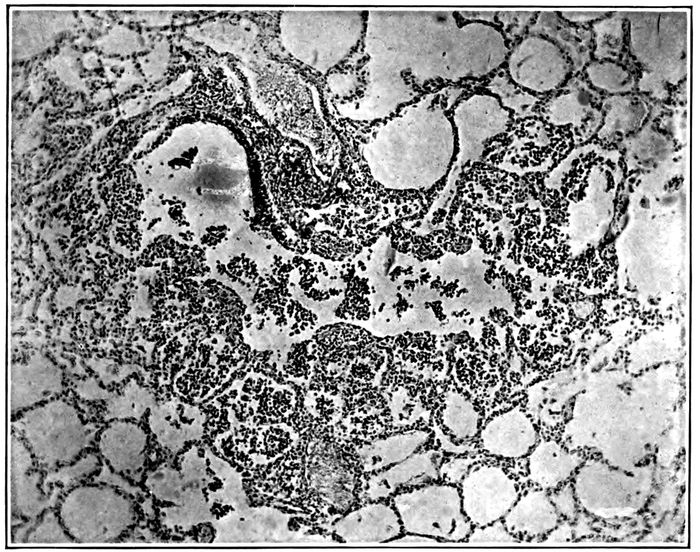

10. Interstitial suppurative pneumonia; interstitial septa are the site of suppuration and lymphatics are distended with purulent fluid; empyema 211

11. Suppurative interstitial pneumonia 212

12. Suppurative interstitial pneumonia 216

13. Suppurative interstitial pneumonia showing a dilated lymphatic 217